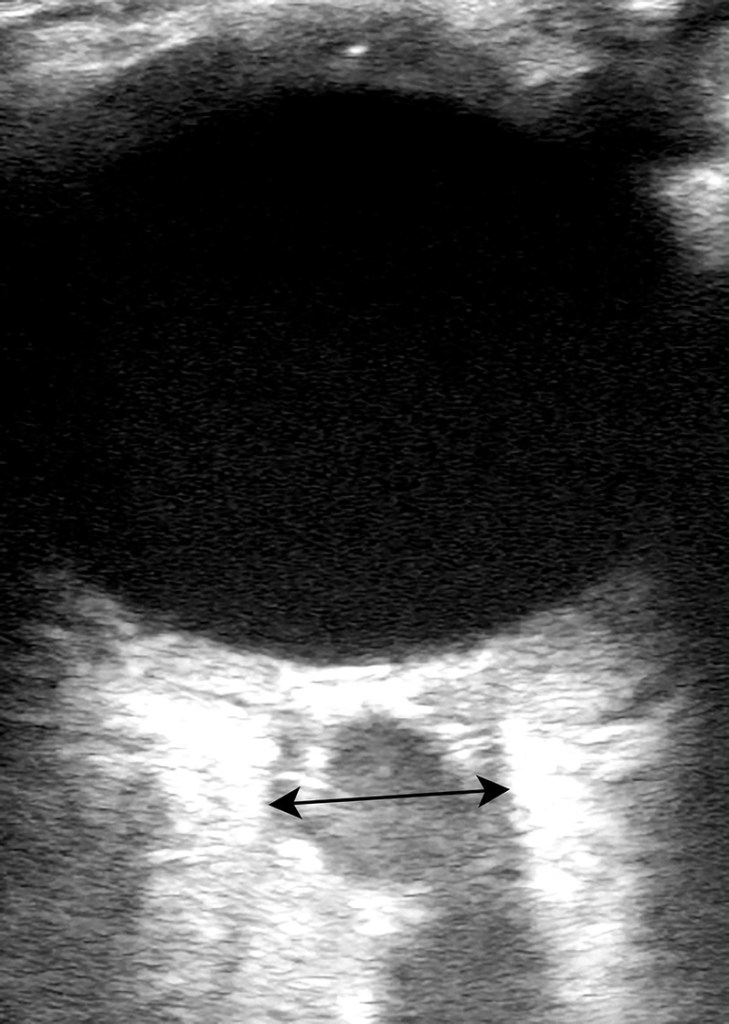

Pigtail Catheter vs Large Bore Chest Tube for Pneumothorax

- We agree with the author’s conclusion. PC performed as well as LBCT in terms of successful drainage and was associated with fewer complications, decreased drainage duration, and decreased length of hospital stay, driven by data on spontaneous pneumothorax.